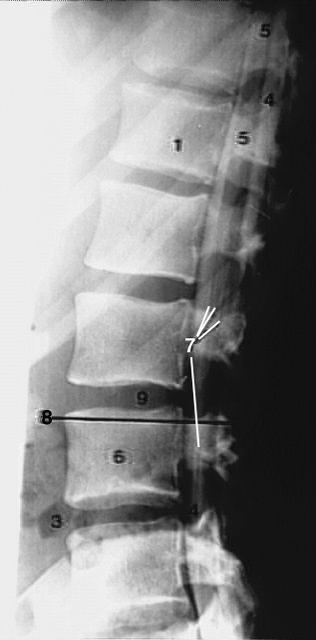

| Back- Lumbar myelogram lateral | |

1. T12 vertebral body. 3. Air in the colon. 4. Contrast in subarachnoid space. 5. Spinal cord. 6. L3 body. 7. Nerve roots of cauda equina. 8. Plane of L3 CT after myelography. 9. Intervertebral disc. |